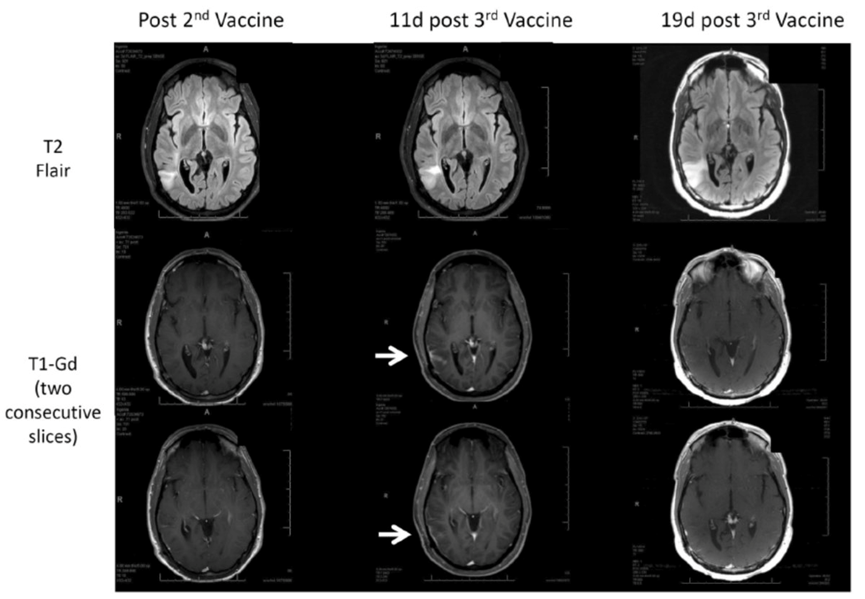

以下是2015年iRANO標(biāo)準中的另一個假性進展(PsP)示例。

免疫療法在神經(jīng)腫瘤學(xué)中的療效評估(iRANO):RANO工作組報告。Lancet Oncol. 2015年11月;16(15)

這是一個接受疫苗療法治療的少突膠質(zhì)瘤患者。第一列顯示了在第二次疫苗后掃描的T2 Flair高信號區(qū)域,與腫瘤相對應(yīng)。下面的兩個T1-Gd掃描顯示沒有異常增強。在第三次疫苗后11天的掃描中出現(xiàn)了異常增強(白色箭頭)。然而,第三次疫苗后19天,異常增強消失了,因此這是另一個假性進展的例子。